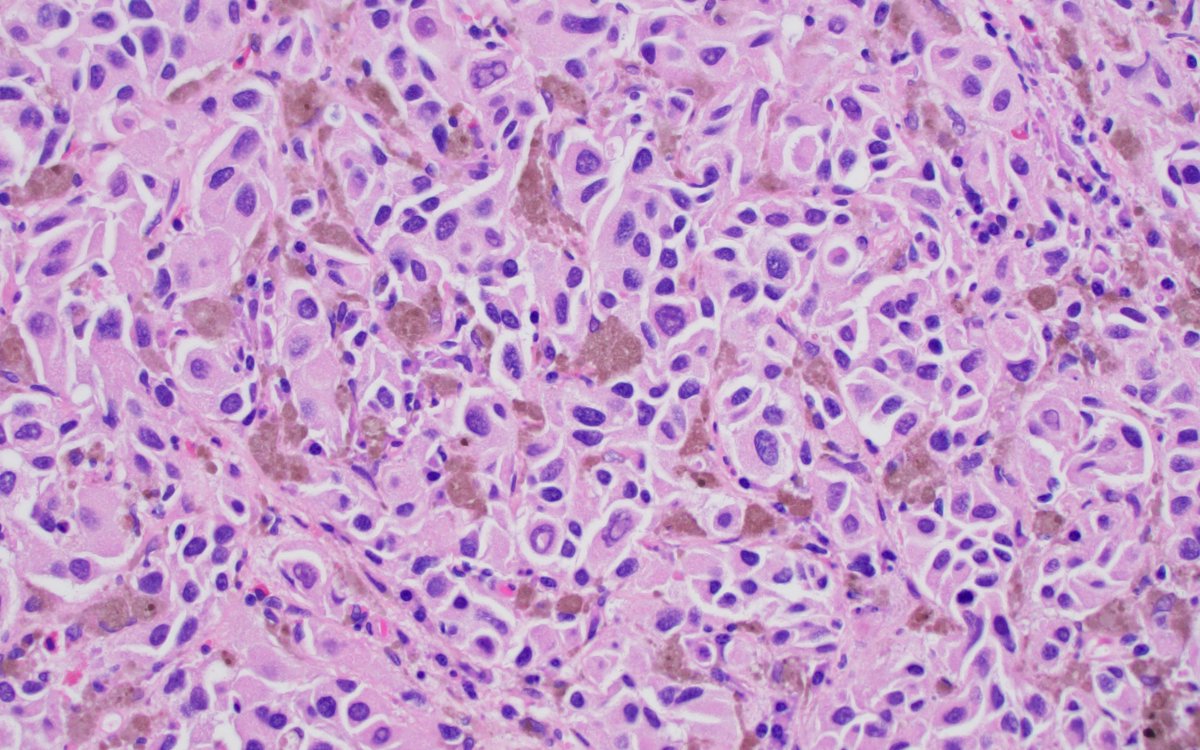

Histology flash card Xanthogranulomatous pyelonephritis Uncommon/rare Destructive inflam process that may resemble RCC Oft assoc with chronic pyelonephritis due to E. coli or Proteus Histo Extensive foamy histiocytes #MedTwitter #PathTwitter